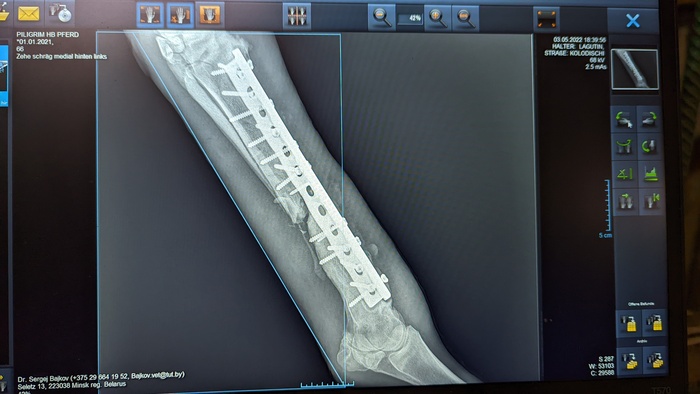

Но несмотря на заметные глазу улучшения, рентгены говорили об обратном. Местные вет врачи, а также многочисленные консультации с лучшими московскими и питерскими клиниками сводились к одному - остеомиелит, проще говоря, кость разрушалась, а не срасталась. На фото рентген спустя 3 месяца после операции

И спустя еще один месяц результат был примерно тот же

С момента операции прошло уже больше 4 месяцев, результата сращивания кости нет, здоровье молодой лошади сильно подорвано антибиотиками, состояние почек можно назвать как "не сегодня, так завтра откажут". Артроз скакательного сустава больной ноги был диагностирован по рентгенам (из-за того, что слишком долго сустав бы зафиксирован гипсом), артроз всех здоровых ножек виден уже снаружи. Не говоря уже о менее значительных изменениях, таких как сутулая спина, зажатые забитые мышцы всего тела, потеря веса